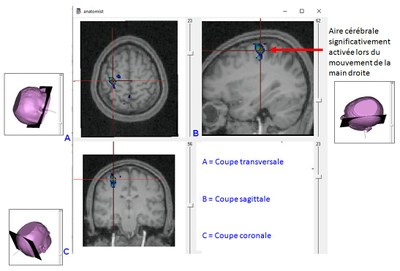

Cerveau et motricité

Activité pédagogique IRM médullaire + IRM cérébral et motricité

Figures et documents activité IRM médullaire + cérébral et motricité

Production bouger main droite.JPG